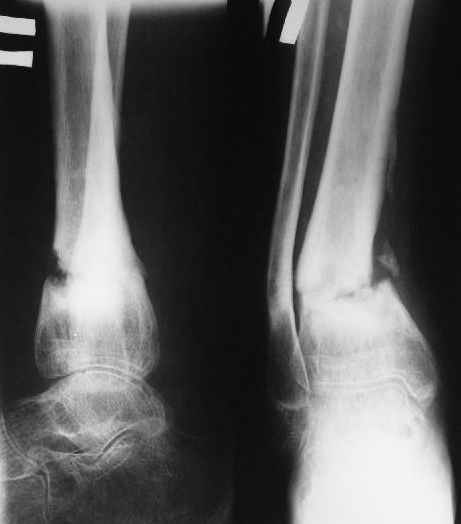

В январе 2005: варусная деформация н\3 голени, болевой с-м, комбинированная контрактура г\стопного сустава, нейропатия м\берцового нерва сохраняется слабость разгибания 1 пальца.

Операции: 1 Клиновидная резекция на вершине деформации м\берцовой кости.

2 Тугоподвижный ложный сустав н\3 б\берцовой кости. Рубцы выполняющие пространство между отломками, канал проксимального отломка иссечены.

Одномоментное устранение деформации, остеосинтез Г-образной пластиной.

Есть даже тень периостальной костной мозоли и сросшийся перелом

малоберцовой кости.

Это сросшийся перелом малоберцовой кости. И ложный сустав

н\3 б\берцовой кости.